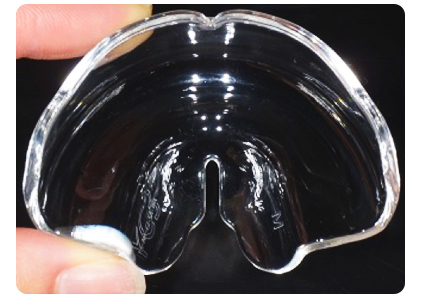

下顎前突の症例に用いる装置です。幼時から小学生までの上顎の成長が小さい場合に新聞などで今話題となっているムーシールドを使用してもらいます(下写真)。この装置は、寝ている間に特殊なマウスピースを装着することにより、舌の力で上顎の成長を促し、下顎の成長を抑えます。当院の小児治療の場合には、8割以上の方がムーシールドのみで治療して、改善しております。